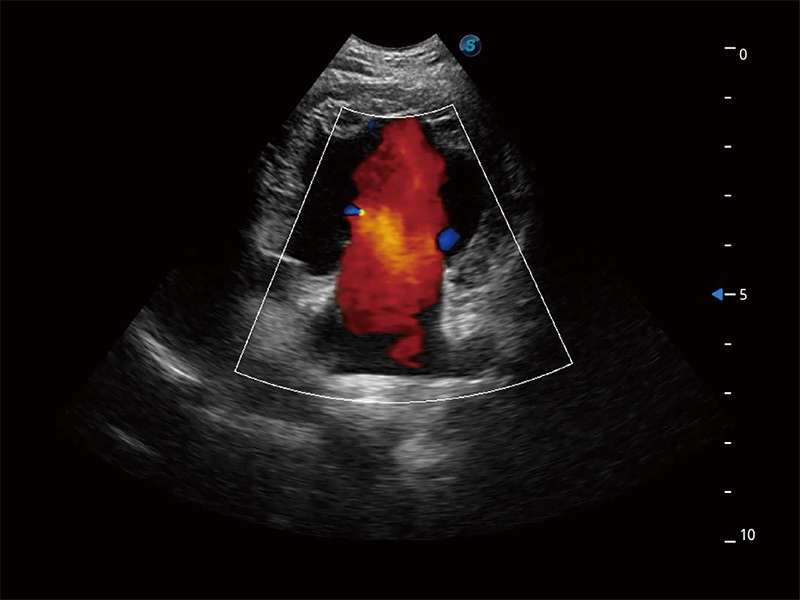

(犬)胎儿主动脉弓立体血流

(犬)二腔心血流